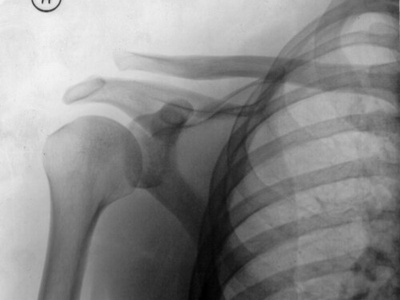

Shoulder

A synovial ball-and-socket where the humeral head fits the glenoid fossa; located at the shoulder. It allows multi-axial movement—flexion, abduction and rotation up to about 180°—and is notable for high mobility but instability and common dislocation risk.